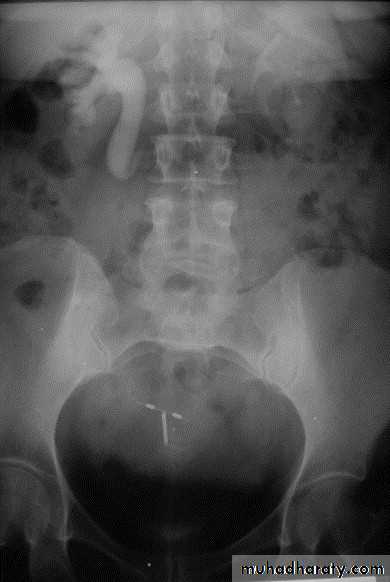

Ureterocele :

Congenital cystic dilatation of lower end of ureter ( intra-mural part) due to pin-hole meatus . May be simple or ectopic .

simple : the orifice is in proper position of bladder ,

Ectopic >> in bladder neck , urethra , uterus & vagina .

IVU :

- There is rounded or elliptical dilatation of lower end of ureter with thin lineal filling defect around it , resembling (cobra head appearance),

- Proximal dilatation of rest of ureter .

- In advanced cases hydronephrosis .

- In obstructed ureterocele , filling defect in the bladder